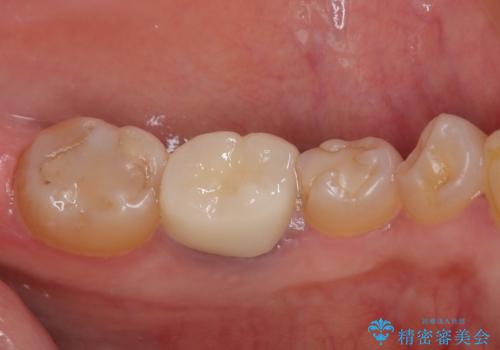

インプラント治療をきっかけに、銀歯を全てセラミックに替えていきました。

人の目を気にせずに、大きく口を開けて笑えるようになりました。